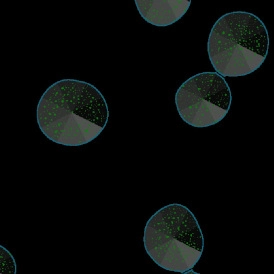

The IF Spheroids App allows a comprehensive analysis of spheroids (as well as organoids and embryoid bodies). It automatically identifies the spheroids and cells based on the nuclei staining and analyzes two additional IF markers. It segments the cells into different cellular compartments, including membrane, nuclei, and cytosol, and further measures the marker expression for each compartment. It can also measure dot markers (if available). It establishes proximity distances for the cells detected within the spheroids, bringing the IF-stained cell populations into spatial context.

App Category 3